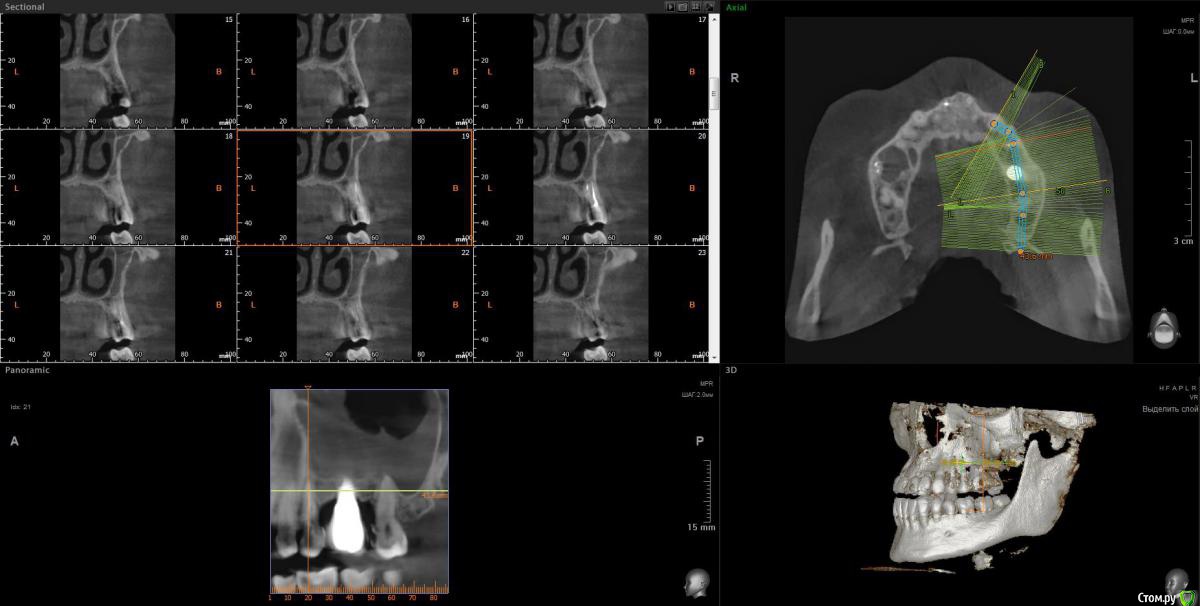

Lunar Опубликовано 8 апреля, 2020 Поделиться Опубликовано 8 апреля, 2020 Добрый день!Подскажите, пожалуйста, можно ли как-то разрулить ситуацию с левой стороной верхней челюсти..2014-2015гг - удаление 6 зуба, синуслифтинг, имплантация, протезирование. Все этапы отдельно. После синуслифтинга воспалилась пазуха и через n-ные промежутки времени делает это до сих пор и вот прямо сейчас в том числе (3 или 4ю неделю не могу с ней совладать). Ранее антибиотики решили вопрос с носовыми кровотечениями, но с остальной симптоматикой помогают лишь временно. Вместе с пазухой болит 7 зуб (из-за нее, или пазуха из-за зуба - один из вопросов..). Пару недель назад на десне над 7ой образовалось воспаление (гнойник). Сейчас десна поджила, зуб ноет тише, болит уже не половина головы, а только в районе пазухи, температура перестала повышаться. За 5 лет болеть все начинало от переохлаждения, само по себе и после стоматологических манипуляций в области импланта и 7 (раза 3 или 4 делали контакты, тк в промежутки все время все забивается).Тк прижало весьма не вовремя, почти все стоматологии закрыты, я буду очень благодарна, если сможете посмотреть снимки ( скрины кт после удаления, после синус лифтинга и недельной давности, только не уверена в правильности проекций..) и сориентировать по вопросам:1. Воспаление в пазухе связано ли с зубами?2. Депульпирование или удаление 7 зуба поможет снять воспаление? если это возможно определить по снимкам.. 3. Можно ли как-то исправить ситуацию в области импланта, в плане того, что заменить царь-коронку на что-то более компактное, чтобы оно начиналось не в складке, а поближе к остальным зубам? Удалять ли имеющийся?. Попробовать повторно нарастить кость и/или десну.. или только менять коронку, чтобы создать нормальный контакт между зубами, снять воспаление, и можно было бы полноценно пользоваться этой многострадальной стороной..С какой стороны мне вообще к этому всему подступиться или лучше не трогать?Заранее большое спасибо! Ссылка на комментарий

wladdX Опубликовано 9 апреля, 2020 Поделиться Опубликовано 9 апреля, 2020 Несколько скринов Ссылка на комментарий

Lunar Опубликовано 9 апреля, 2020 Автор Поделиться Опубликовано 9 апреля, 2020 Несколько скринов25_1.jpg25_2.jpgimp_1.jpgimp_2.jpg27_1.jpg27_2.jpgспасибо за скрины Ссылка на комментарий

Irouil Опубликовано 9 апреля, 2020 Поделиться Опубликовано 9 апреля, 2020 https://yadi.sk/d/FRKX9i80axqaUgПосмотрел я Ваше КТ. На мой взгляд, проблема чисто ЛОРовская, но... ЛОР врач может придраться к состоянию в полости рта и формально будет прав, поэтому Сначала проверить на витальность 7ку (вероятнее всего все же придётся депульпировать) Клинически осмотреть 5-ку (стоматологу терапевту). Потом к лору. Имплантат к пазухе вообще не имеет никакого отношения 1 Ссылка на комментарий